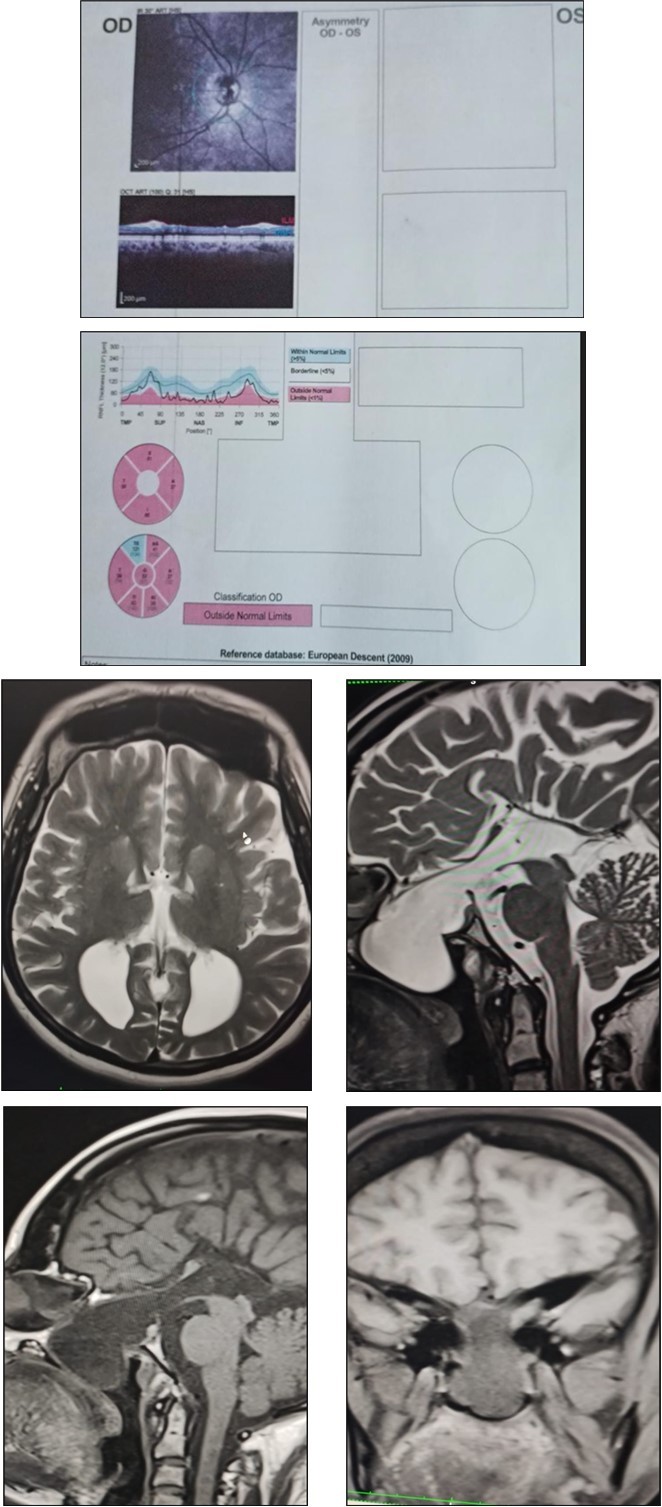

MRI showed parallel running lateral ventricles and colpocephaly (Racing Car appearance), large central sphenoethmoidal meningoencephalocoele with large bony defect in anterior sellar floor, planum sphenoidale and ethmoid bone. Herniated sac (4.1x3.5x2.6) contains bilateral optic nerves olfactory nerves, infundibulum of pituitary gland and csf. Pthisis bulbi of left eye noted.Figure 1

Figure 1.Fundus Images and OCT – right optic atrophy ; pale optic disc

Fundus Images and OCT – right optic atrophy ; pale optic disc